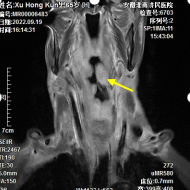

患者脑血管病变引发的慢性微量出血。

图解:磁敏感加权图像中黄色箭头指示的黑色圆点为脑内出血灶。